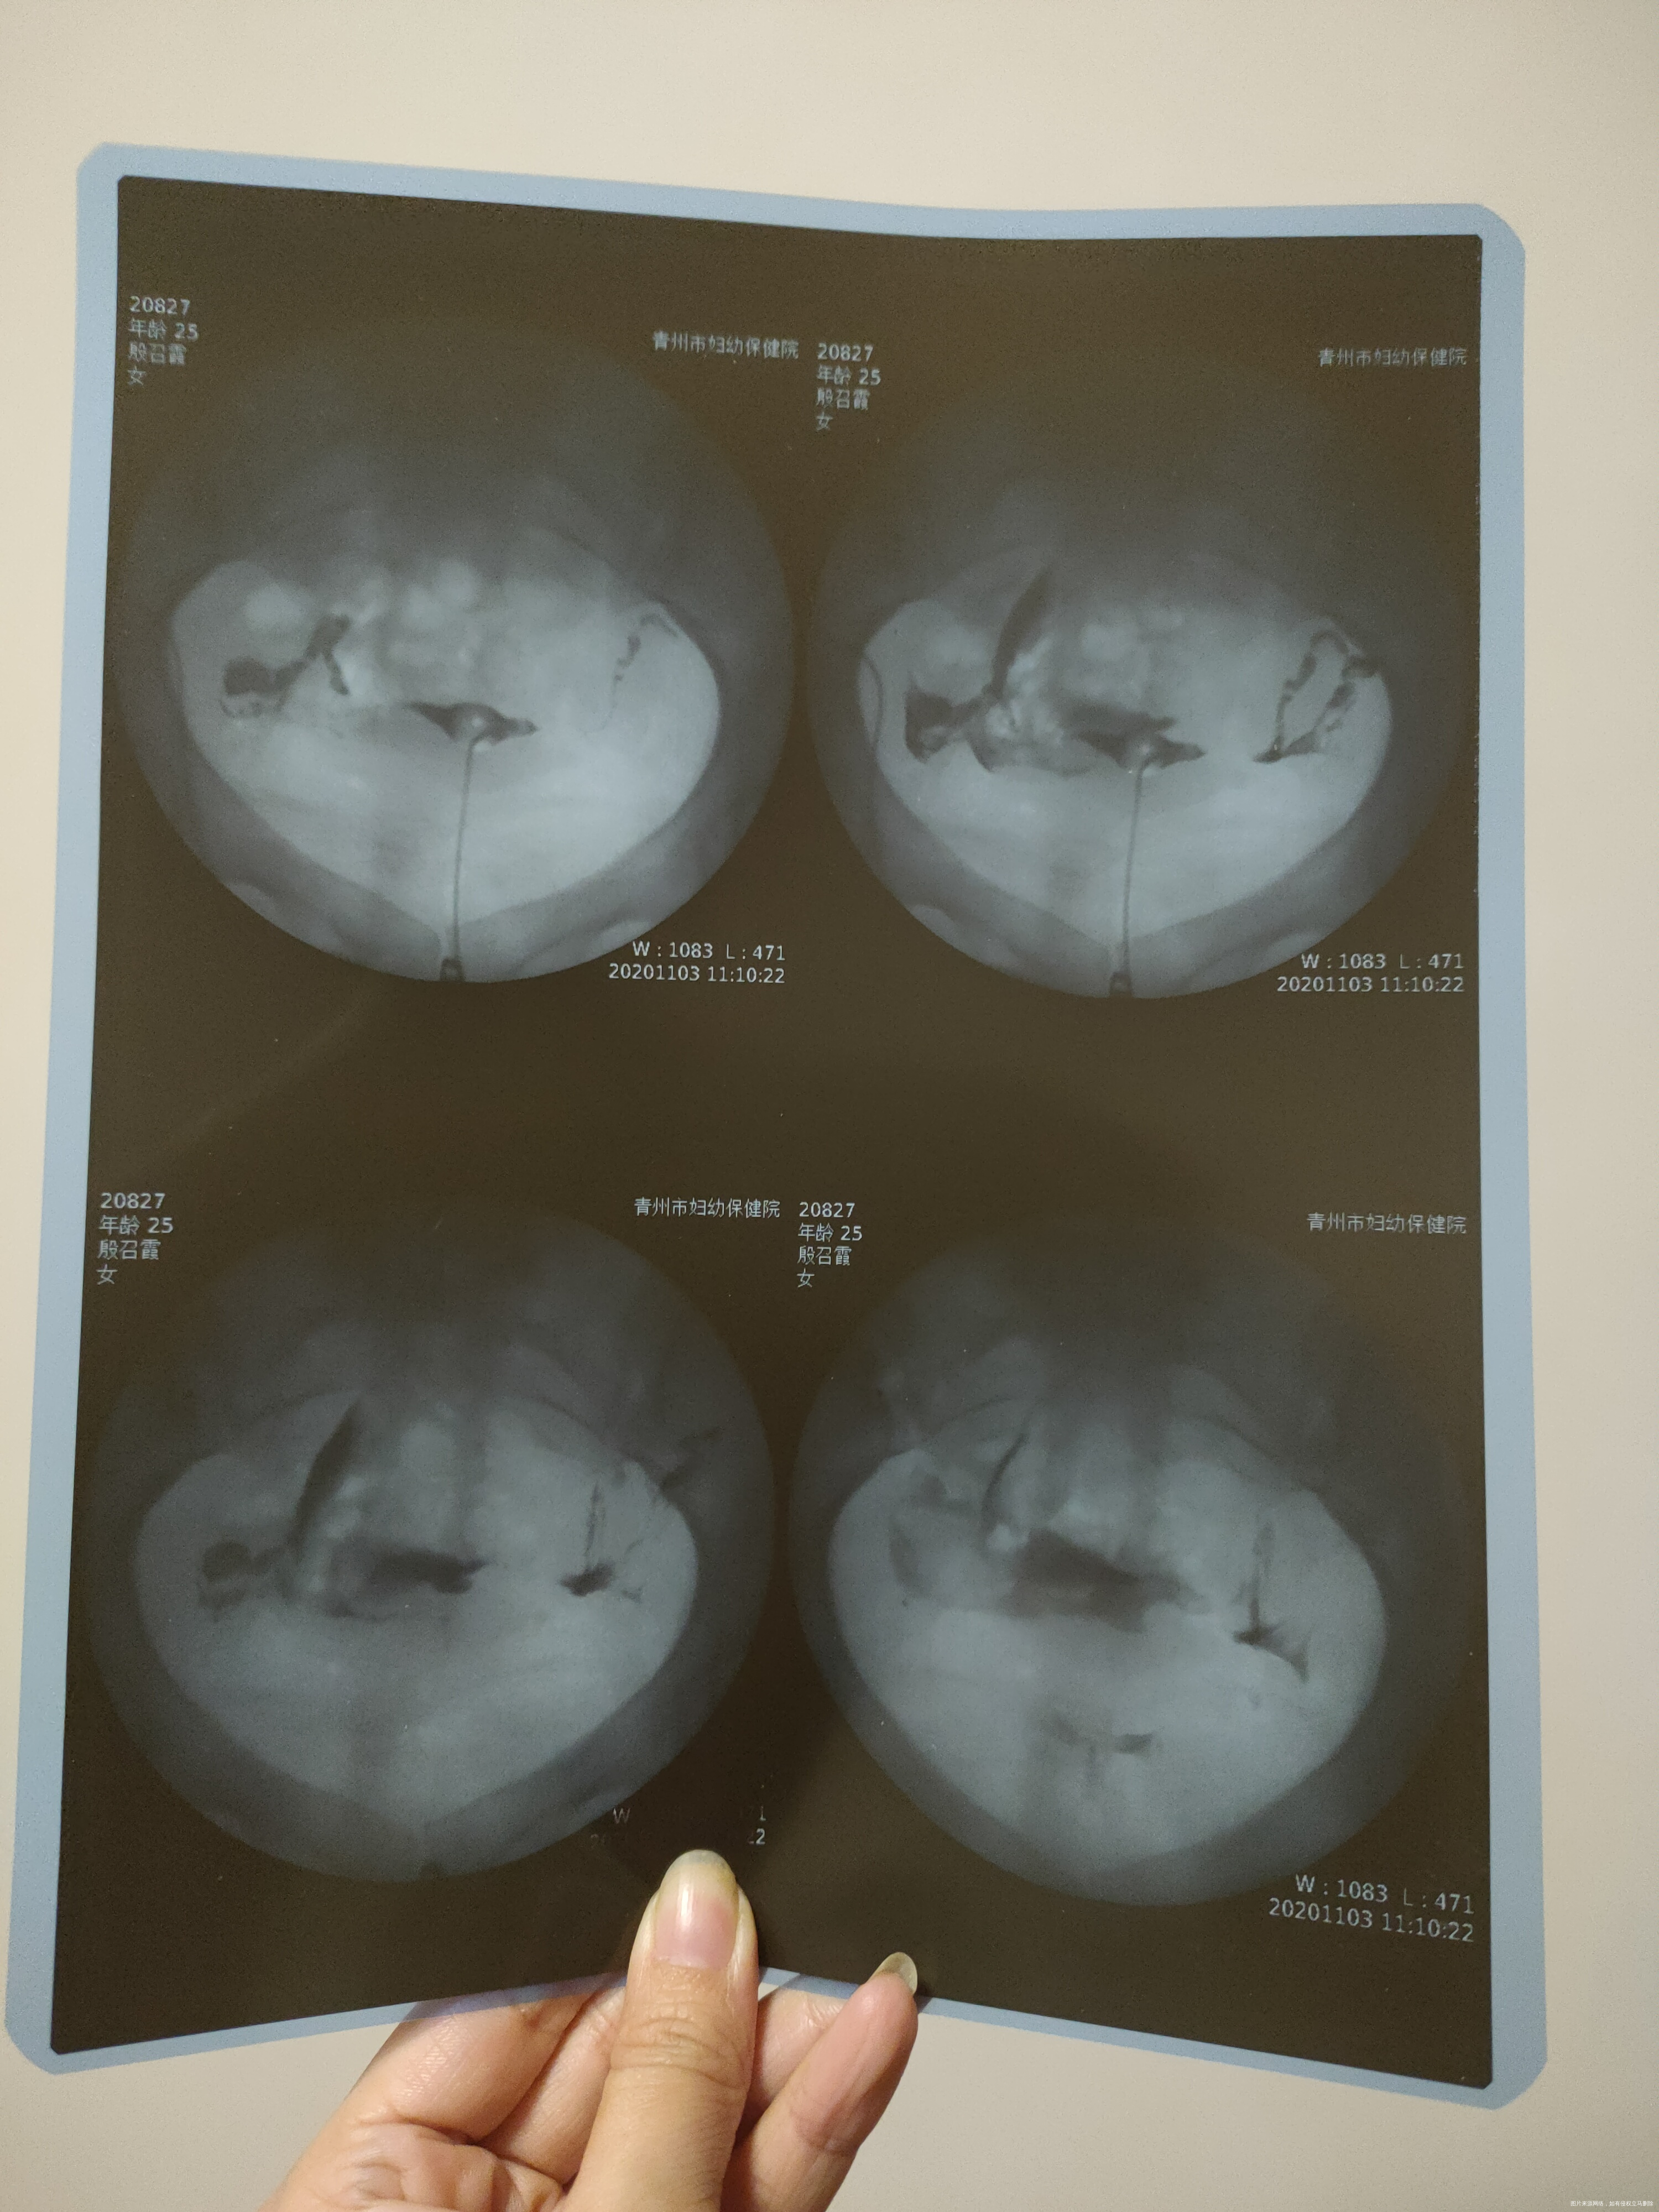

检查性激素六项、B超卵泡检测确诊为多囊,做过输卵管造影检查,显示双侧输卵管不完全堵塞,现在正在促排中,想咨询一下输卵管问题严重吗?

双侧输卵管通而不畅,输卵管管腔有炎症粘连,建议通液后再促排,不然增加宫外孕的风险。

你好,慢性的盆腔炎造成的输卵管通而不畅,容易增加宫外孕的风险,所以建议先治疗盆腔的慢性炎症后再做一次输卵管的检查,确保输卵管通常之后再做排卵处理,避免宫外孕的风险,应该更为安妥。25岁很年轻的,有时间治疗,放松心情,就有自然受孕机会的。供参考。祝好孕!

你好,看片子输卵管情况不算太好,末端应该有黏连,这种情况有宫外孕的风险。建议第一加强锻炼,增强体质,第二中药辅助治疗盆腔炎症。试怀孕同时要心态好